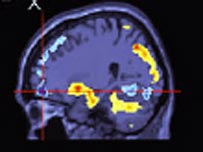

Cérebro de quem sofre com TOC tem estruturas diferentes

Pesquisadores da Universidade de Cambridge, na Grã-Bretanha, descobriram que exames de ressonância magnética do cérebro podem ajudar a revelar pessoas com predisposição genética a desenvolver o transtorno obsessivo-compulsivo (TOC).

Pessoas que sofrem com o problema e seus familiares mais próximos possuem uma estrutura cerebral com um funcionamento particular, dizem os cientistas, em artigo publicado na revista científica Brain.

Os cientistas associaram isso à queda de massa cinzenta em regiões do cérebro responsáveis pela supressão de respostas motoras e hábitos.

"A deficiência da função cerebral nessas regiões podem contribuir com os comportamentos compulsivos e repetitivos que são característicos do TOC", afirmou Lara Menzies, da equipe de pesquisadores.